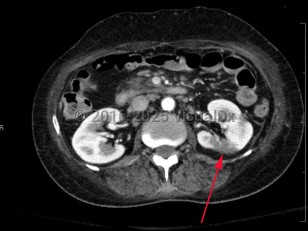

Imaging Studies image of Renal infarction - imageId=8361316. Click to open in gallery.  caption: '<span>Axial image from enhanced CT scan of the abdomen showing a wedge-shaped peripheral region of low attenuation in the posterior aspect of the mid left kidney.</span>'

Axial image from enhanced CT scan of the abdomen showing a wedge-shaped peripheral region of low attenuation in the posterior aspect of the mid left kidney.